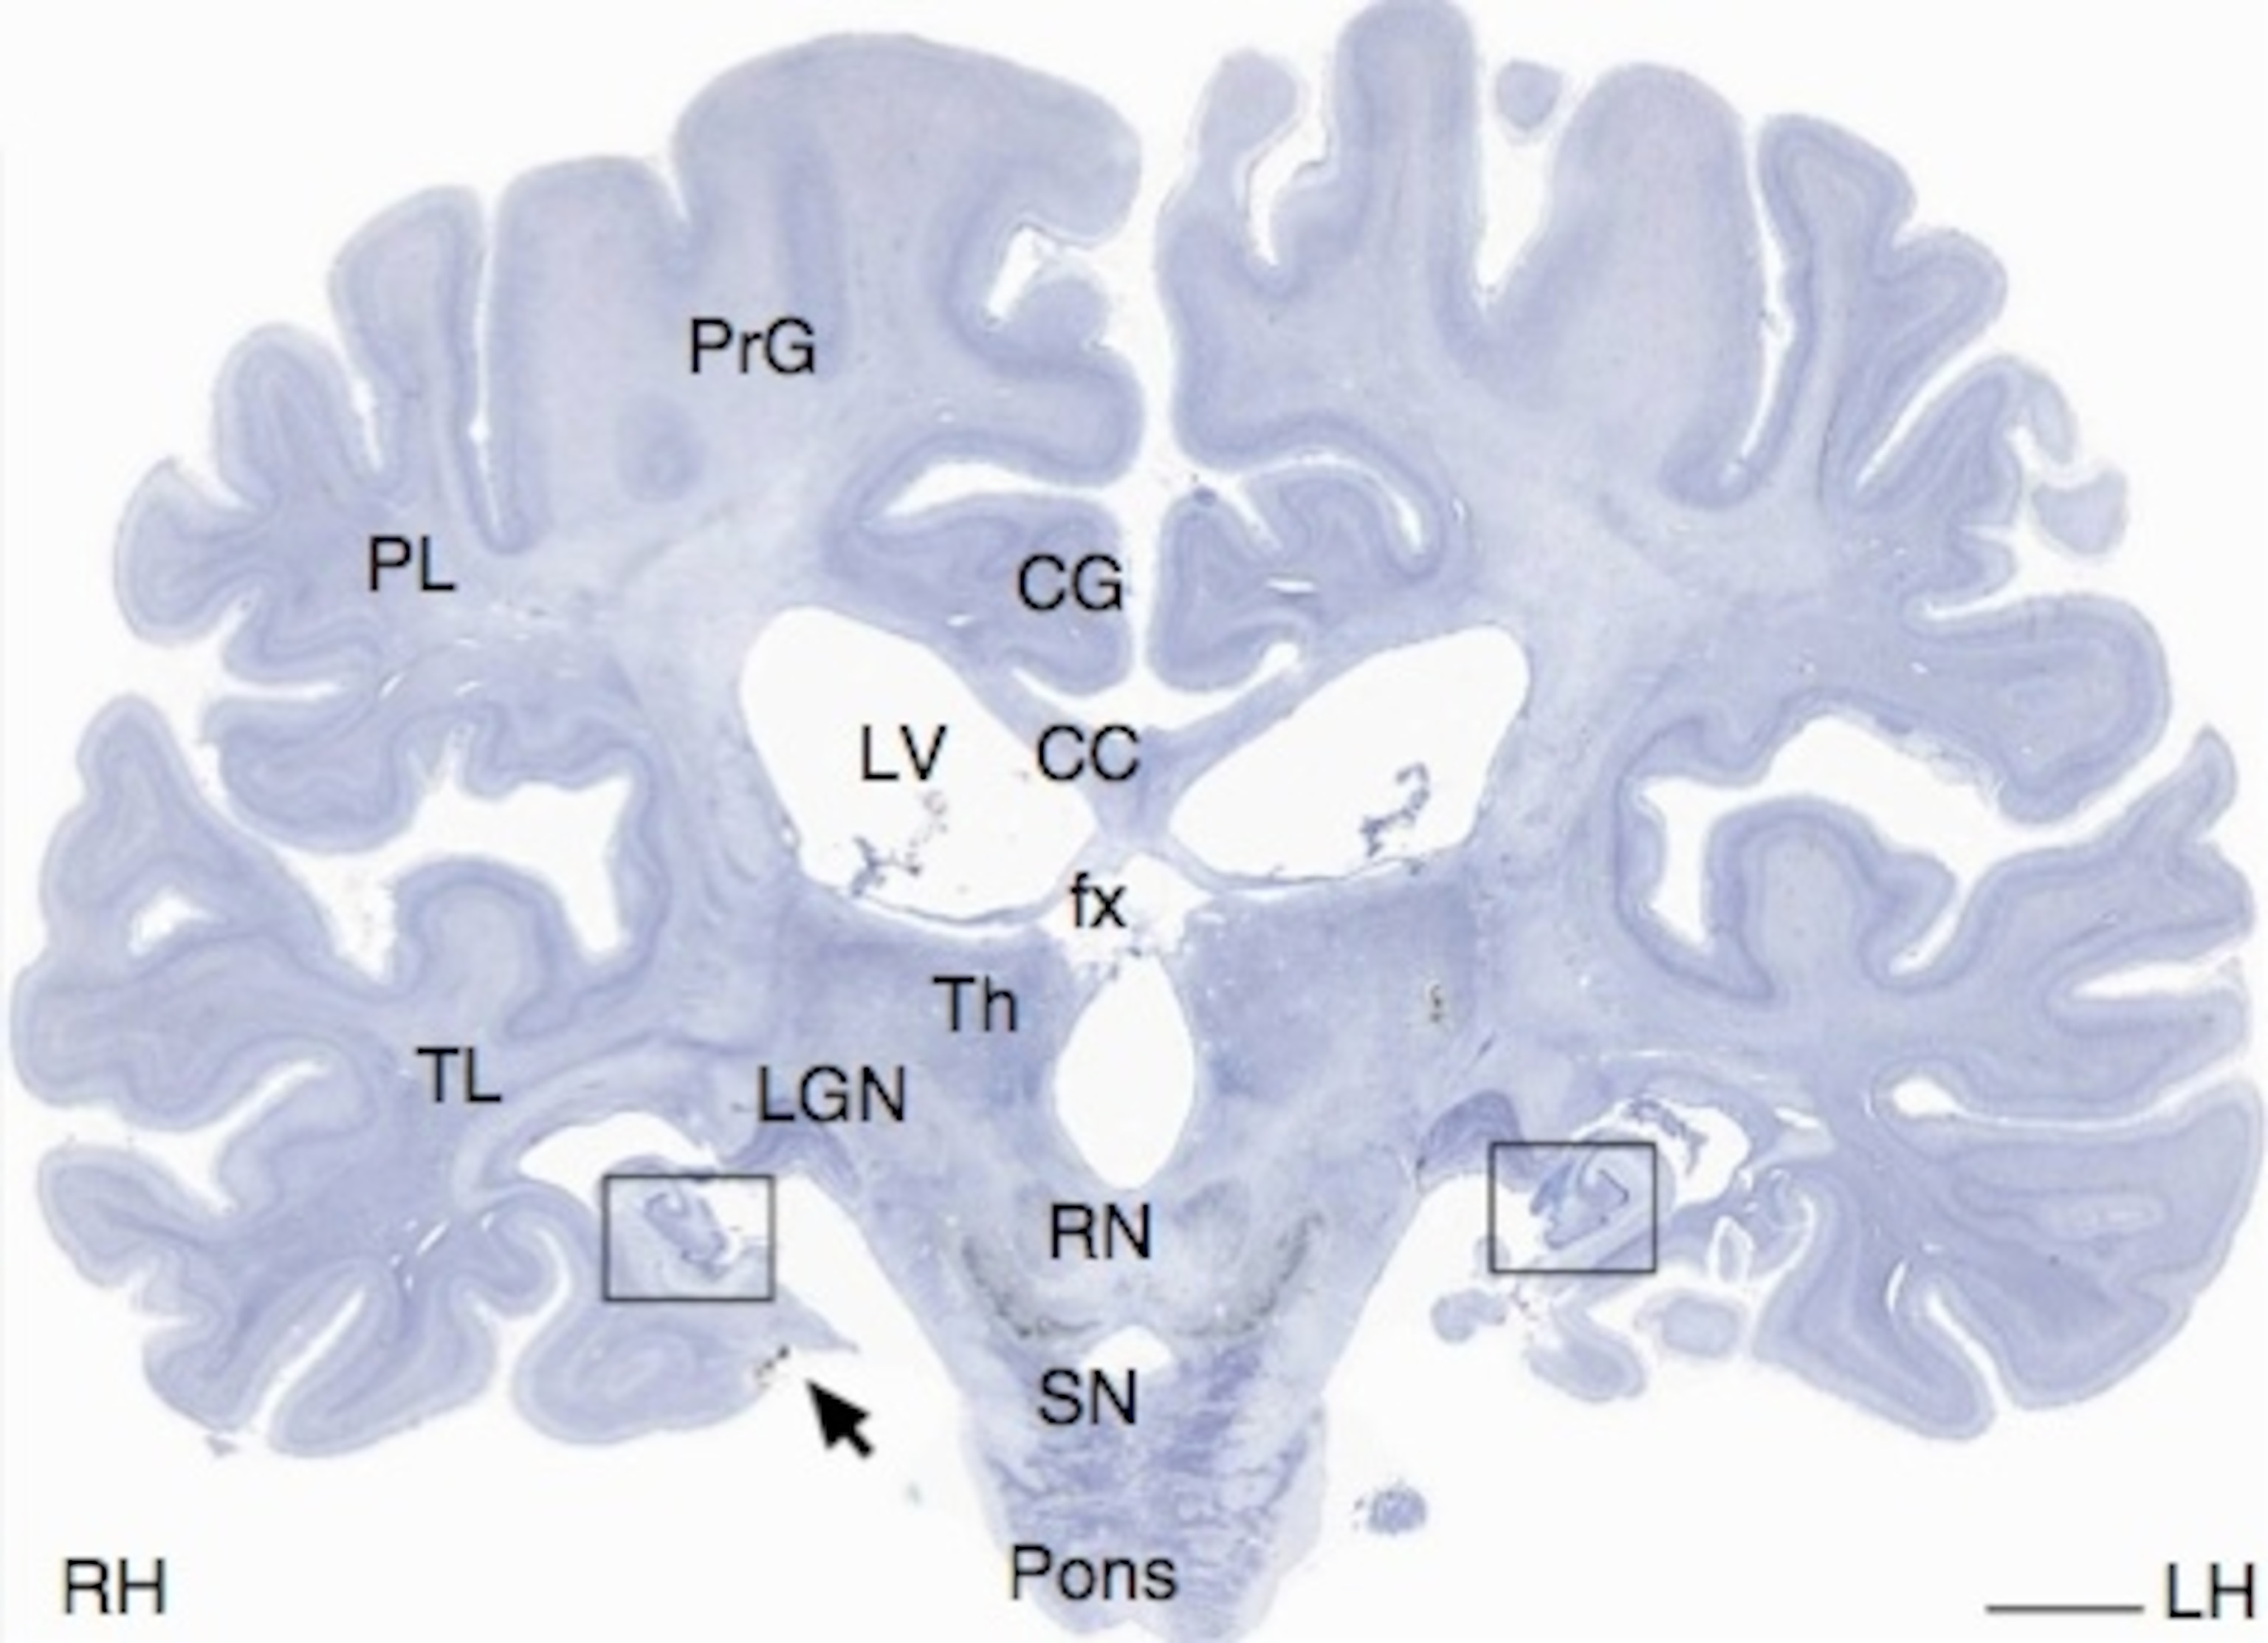

Click here to see what one slice looks like in the atlas. If you use the arrows to zoom in to the two small seahorse-like regions at the bottom of the slice (see the boxes on the picture at right), you’ll be looking at what was left of H.M.’s hippocampus. Although most emphasis on H.M. has focused on his missing hippocampus, brain-imaging studies have shown since the late 1990s that he actually retained about 50 percent of this region. The new resource confirms this, and also allows researchers to look closely at individual hippocampal cells, providing a fine-grained molecular view that is not possible with brain imaging.